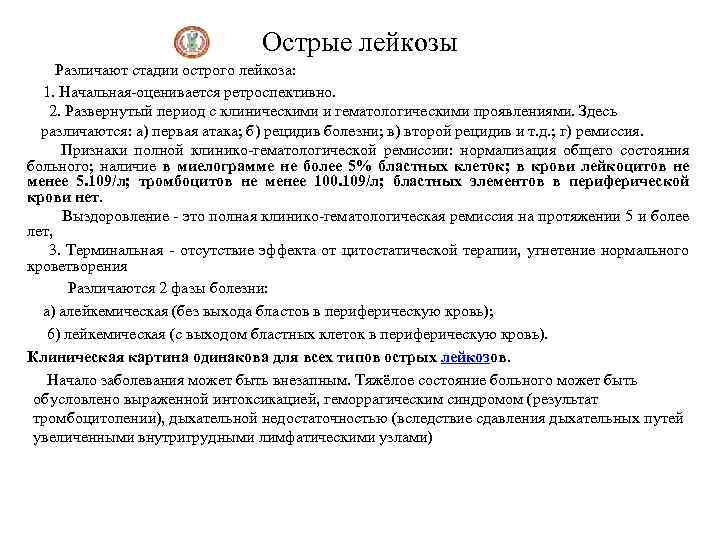

Острые лейкозы Различают стадии острого лейкоза: 1. Начальная-оценивается ретроспективно. 2. Развернутый период с клиническими и гематологическими проявлениями. Здесь различаются: а) первая атака; б) рецидив болезни; в) второй рецидив и т. д. ; г) ремиссия. Признаки полной клинико-гематологической ремиссии: нормализация общего состояния больного; наличие в миелограмме не более 5% бластных клеток; в крови лейкоцитов не менее 5. 109/л; тромбоцитов не менее 100. 109/л; бластных элементов в периферической крови нет. Выздоровление - это полная клинико-гематологическая ремиссия на протяжении 5 и более лет, 3. Терминальная - отсутствие эффекта от цитостатической терапии, угнетение нормального кроветворения Различаются 2 фазы болезни: а) алейкемическая (без выхода бластов в периферическую кровь); 6) лейкемическая (с выходом бластных клеток в периферическую кровь). Клиническая картина одинакова для всех типов острых лейкозов. Начало заболевания может быть внезапным. Тяжёлое состояние больного может быть обусловлено выраженной интоксикацией, геморрагическим синдромом (результат тромбоцитопении), дыхательной недостаточностью (вследствие сдавления дыхательных путей увеличенными внутригрудными лимфатическими узлами)